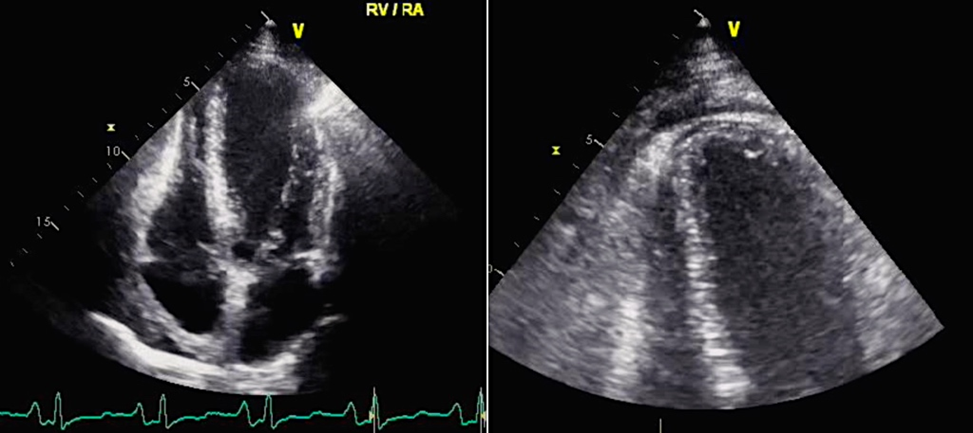

При проведении ЭхоКГ могут быть выявлены ранние признаки констриктивного перикардита, такие как парадоксальное диастолическое движение межжелудочковой перегородки (МЖП) (Приложение А3, рис. А3-1) [83].

Трансторакальная ЭхоКГ является надежным способом диагностики констриктивного перикардита: обнаружение утолщения ≥3 мм обладает 95-процентной чувствительностью и 86-процентной специфичностью (Приложение А3, рис. А3-3) [3].

Более ценной находкой будут участки адгезии, которые при двумерной ЭхоКГ проявляются втяжением перикарда вслед за миокардом во время систолы без изменения эхо-негативного пространства между ними. Обнаружение распространенных участков адгезии перед легочной артерией и за боковой стенкой левого желудочка (при М-модальном исследовании за стенкой левого желудочка) говорит о генерализованном утолщении листков околосердечной сумки.

Парадоксальное движение межжелудочковой перегородки во время ранней диастолы является характерным для пациентов с констриктивным перикардитом. Во время вдоха движение происходит в сторону левого желудочка, во время выдоха — в противоположном направлении [3]. При М-модальном исследовании это проявляется выемкой в раннюю диастолу при определении движения межжелудочковой перегородки, что напоминает нарушения сокращения-расслабления миокарда, наблюдаемые при блокаде левой ножки пучка Гиса или электростимуляции правого желудочка (Приложение А3, рис. А3-4). При определении этого признака двухмерной ЭхоКГ чувствительность составляет 62%, а специфичность — 93% [3]. Использование допплеровской визуализации тканей можно существенно увеличить чувствительность метода до 82,5% [122].